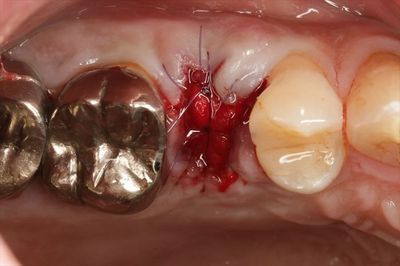

割れた頬側部分を取り除いた状態です。

続いて口蓋側部分の抜歯に進みます。